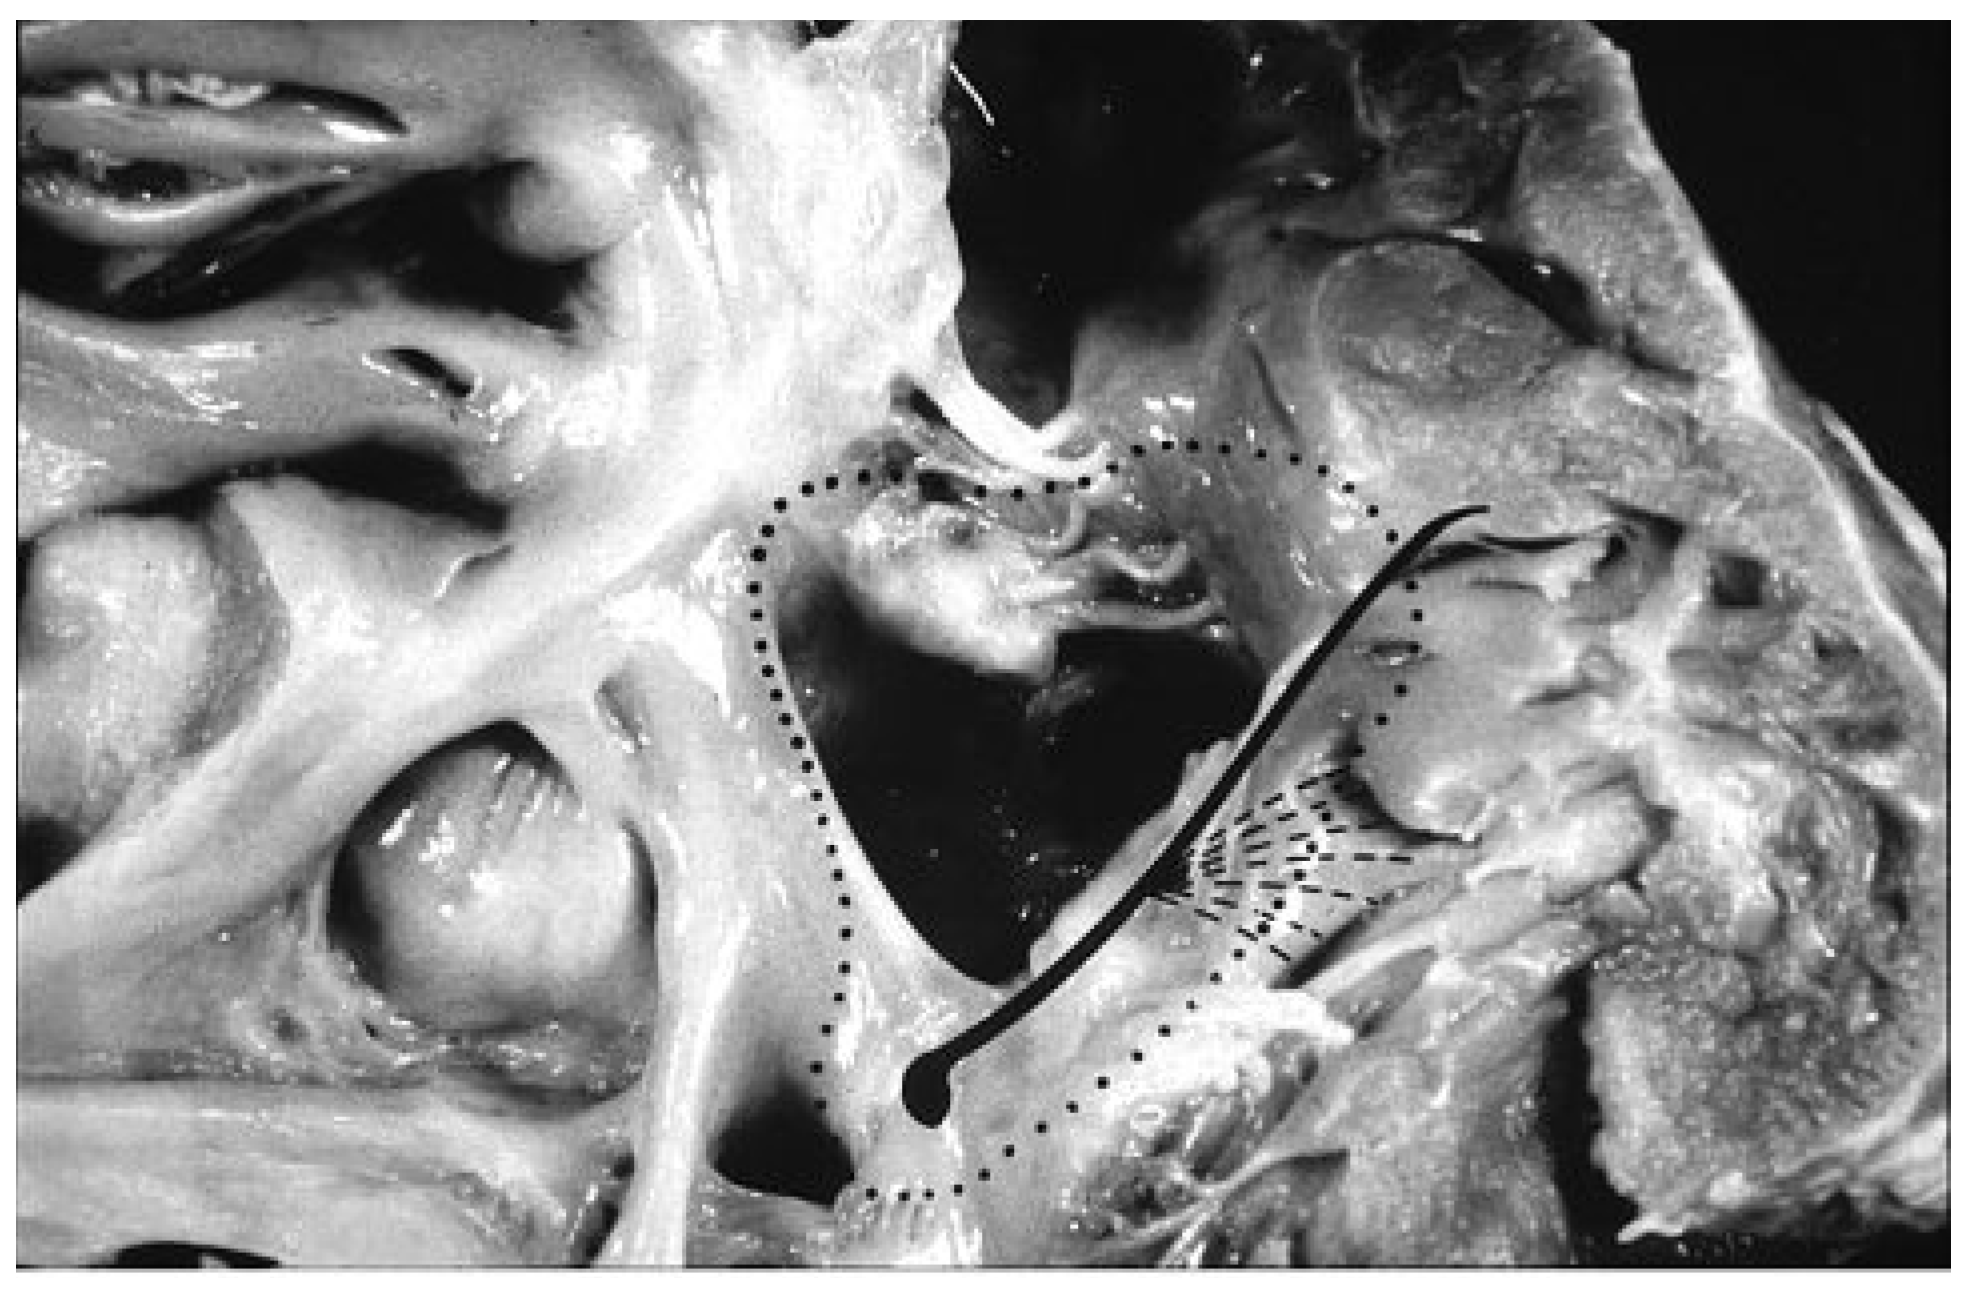

Following improvements in anaesthesiology and myocardial-cerebral protection during cardiac arrest, which rendered operations feasible even in neonates [24], a sound knowledge of the anatomy of complex congenital heart diseases appeared to be a prerequisite for optimising clinical diagnosis and improving surgical repair. Implementation of a cardiac registry of congenital heart disease specimens, collected since the beginning of paediatric cardiology, allowed the study of the whole anatomical spectrum of various defects. The anatomical collection represented the interface of paediatric cardiologists and cardiac surgeons with the CV pathologist, for the quality control of both clinical diagnosis and surgical treatment as well as for planning new technical solutions for diagnosis or repair. The segmental approach (atria, ventricles and great arteries) was introduced as the best way to clear up the difficulty of diagnosing complex congenital heart diseases [25], with the aim of reconstructing, by surgery, separated pulmonary and systemic circulations in a correct sequential manner. The identification of the precise course of the conduction system through histological serial sections virtually removed all the risks of av block during closure of septal defects (Figure 3), by guiding the hand of the surgeon in suturing the patch [26].

Figure 3.

The course av conduction system in av canal malformation, as delineated by histological investigation: the dotted line indicates how to insert the patch to avoid av block (surgical view).